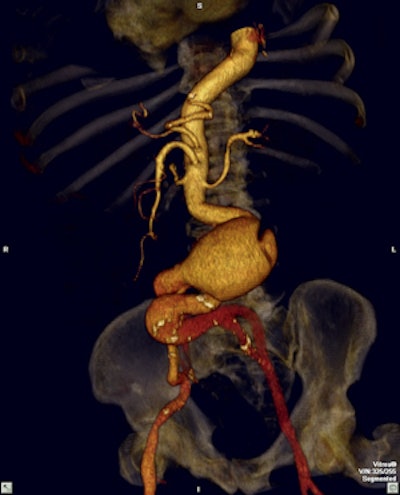

Leading hospitals in Colombia make use of the latest software to visualize and analyze 2D, 3D, and 4D images. All images courtesy of the Asociación Colombiana de Radiología.However, in today's ever-changing world with the discovery of novel techniques and technologies and new forms of practice and care models, there is an underlying concern about what this could mean for the future of the practice of radiology.

Musculoskeletal imaging is an area of special expertise among Colombian radiologists."It is an inexact science in which the higher the number of experts to join in the process, the better the result and lower the load of individual responsibility," he continued. "The radiologist is essential and irreplaceable in this regard."